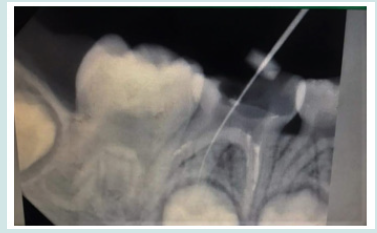

A girl child of 6 years had come to the department of pedodontic and preventive dentistry at the dental institution with a chief complaint of pain in the in the lower left back tooth region of jaw since past one week. On clinical examination she was having deep occlusal caries with respect to tooth number 85. Radiographically, the caries had progressed to the pulp chamber. The presence of third root/ additional root was also revealed. The diagnosis of chronic irreversible pulpitis with 85 was made (Figure 1). It was also found through radiograph that extra root was present with respect to 84 and 75 which were healthy. The tooth was isolated and access opening was done under local anesthetia and all the canals were located. Those were mesiobuccal, mesiolimgual, distobuccal and distolingual with the working length of 15mm in all the four canals (Figure 2). Cleaning and shaping of all the canals were done. Followed by obturation with metapex (Figure 3). The cavity was then sealed with permanent restorative material followed by stainless steel crown cementation.